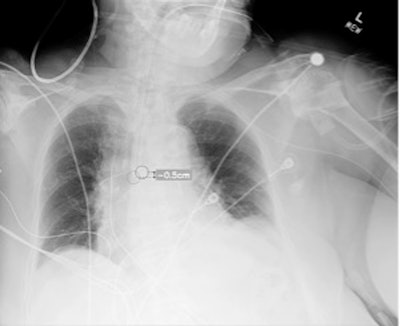

Plain chest radiograph showing overlay from Critical Care Suite, with segmentation of ETT, identification of tube tip and carina, and calculation of distance between them.Critical Care

The researchers gathered 400 chest x-rays of intubated adult patients from three hospitals from a range of clinical settings, including the intensive care units and emergency departments. A panel of thoracic radiologists classified each image by tube placement as correct, too low (distal), or too high (proximal), with correct ETT position defined as the tip located 3 to 7 cm above the carina, in line with established guidelines. Out of the 400 images, 209 were classified as well-positioned, 56 as too high, and 134 as too low.